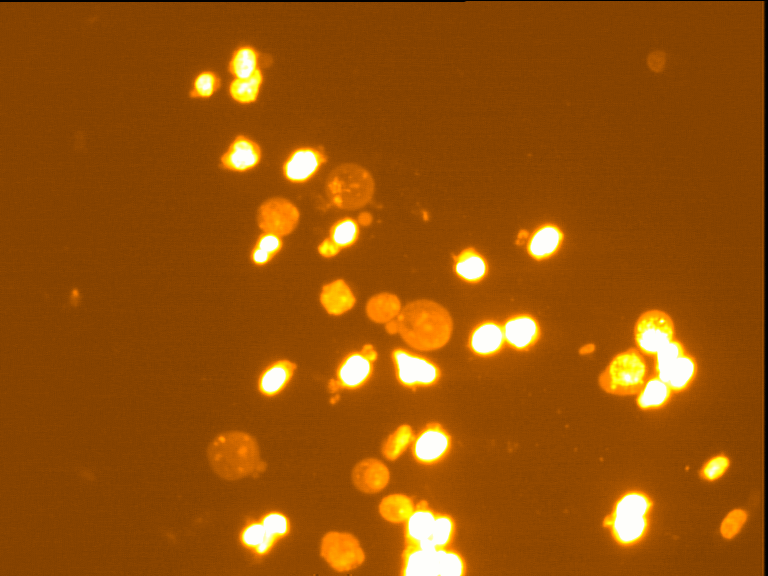

Fig. 4 through 6 show the morphological features of Raji cell sub-lines exposed to DOX, indomethacin, or verapamil. Some of the reversal agents significantly increased the frequency of apoptotic cells compared with control cells. Thus, the P-gp reversal agents were able to overcome apoptotic resistance in the NHL cell-line model. Apoptotic cells in the controls contributed approximately 10% of the whole population (i. e., 61/600 x 100 = 10.16% for TK+ and 69/600 x 100 = 11.5% for TK-). After exposure to the P-gp reversal agents, apoptic cells increased to 22.3% with indomethacin and to 43% with doxorubicin in TK+ cells. In TK- cells, apoptic cells increased from 11.5% to 26.8% and 75.7% with indomethacin and doxorubicin, respectively.

Fig. 5: Morphological features of Raji TK+ cells after treatment with indomethacin (1), verapamil (2) and DOX (3). In each row, left images show intact cells, middle images show apoptotic cells, and right images show necrotic cells as they appeared under the microscope X 200

Fig. 6: Morphological features of Raji TK- cells after treatment with indomethacin (1), verapamil (2), and DOX (3). In each row, left images show intact cells, middle images show apoptotic cells, and right images show necrotic cells as they appeared under the microscope X 200